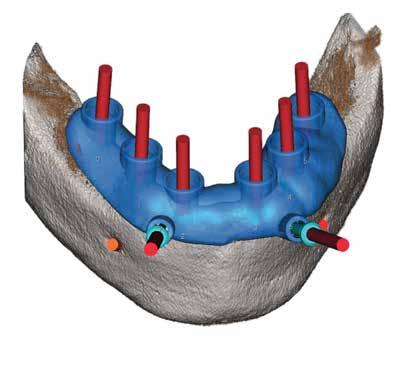

Let's Go To DigitalMultysystem Full Digital Workflow provides different solutions: from anamnesi to surgery, from model scanning to prosthesis with Multysystem 3D guided surgery software, hardware, training tutoring and partial coaching by our experts.

iRES® COMPLETE SOLUTION FOR ORAL SURGERY

In 2011, a Highly Professional Team of Scientists and industrial experts In the field of dentistry created iRES® company. Since that moment “An innovative approach to dental products was created”.

Based in Switzerland, iRES® is a European ISO 13485 certified company specialized in developing, manufacturing and distributing a wide range of medical devices for oral surgery.

Our products include regenerative materials (bone substitutes), implant systems, guided surgery, custom prosthetics, dedicated surgical instruments for the correct insertion of devices and much else.